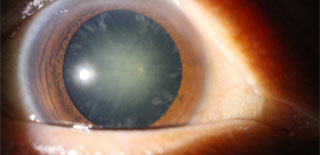

簡單認識白內障手術是什麼?白內障是指眼球內的晶體混濁,導致視力不清,情況就如一部相機的鏡頭受損,不能拍出清晰的照片。如要改善視力,必須把渾濁液晶體清除,再植入-片人工晶片,藉着個人化的人工晶片選擇,不但能改善視力,更能達致減少近視、遠視、散光,以致治療老化的效果。

白內障手術前(左圖) 和後 (右圖)

眼科專科鄧維達醫生表示,現今的白內障手術,傷口較以往的手術大大縮小,以微創手術方式使用超聲波乳化技術,將混濁的晶體清除,再經由可捲曲的人工晶片植入眼內,手術便告完成。手術一般10至15分鐘左右,大部份可於表層局部麻醉(topical anaesthesia) 的方式進行,大多不需縫針或進行注射,讓手術過程更舒適快捷。